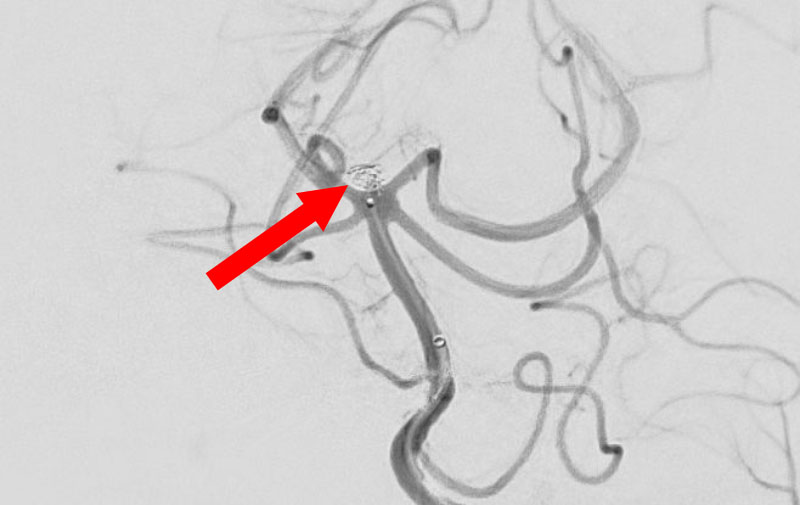

'25年11月

くも膜下出血

右内頚動脈後交通動脈

分岐部動脈瘤破裂

60代

救急外来

No.1593 手術前

No.1593 手術中

No.1593 手術後